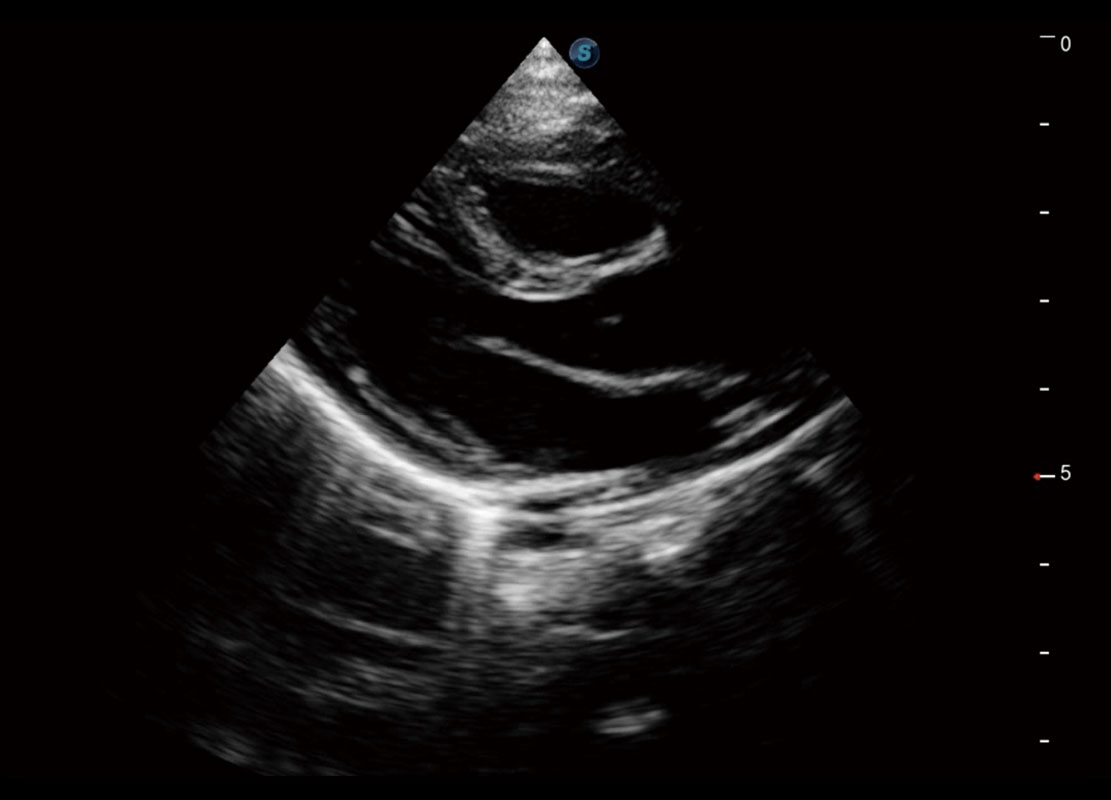

新生儿脊髓圆锥

新生儿心脏